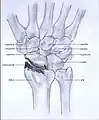

Stages

Post-traumatic osteoarthritis can be classified into four stages.[1][6] These stages are similar between SLAC and SNAC wrists. Each stage has a different treatment.

- Stage I: the osteoarthritis is only localized in the distal scaphoid and radial styloid.

- Stage II: the osteoarthritis is localized in the entire radioscaphoid joint.

- Stage III: the osteoarthritis is localized in the entire radioscaphoid joint with involvement of the capitolunate joint.

- Stage IV: the osteoarthritis is located in the entire radiocarpal joint and in the intercarpal joints. It also may involve the distal radio-ulnar joint (DRUJ).

Stage I

Stage II

Stage III

Stage IV